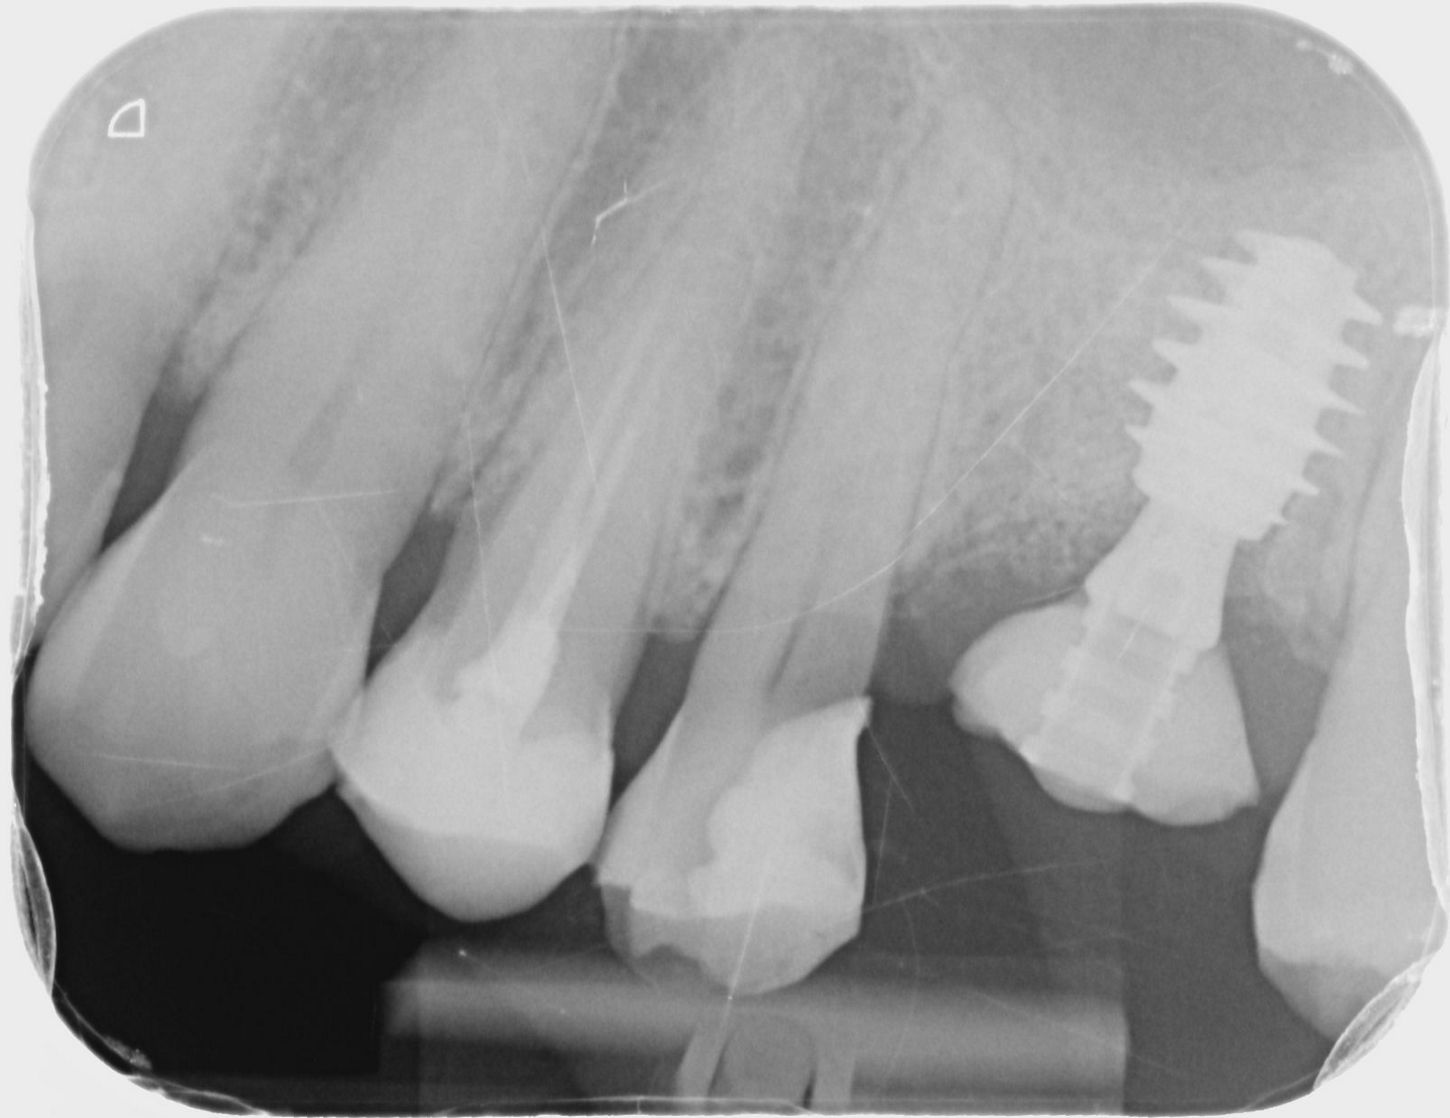

Initial situation

The patient was diagnosed by 3D CT scan and radiograph during a routine control of a classic first molar.  The clinical signs necessitated tooth extraction followed by immediate implantation, socket gap filling and placement of a sealing socket abutment to support anatomical structures.

1. Radiograph of initial situation.

1